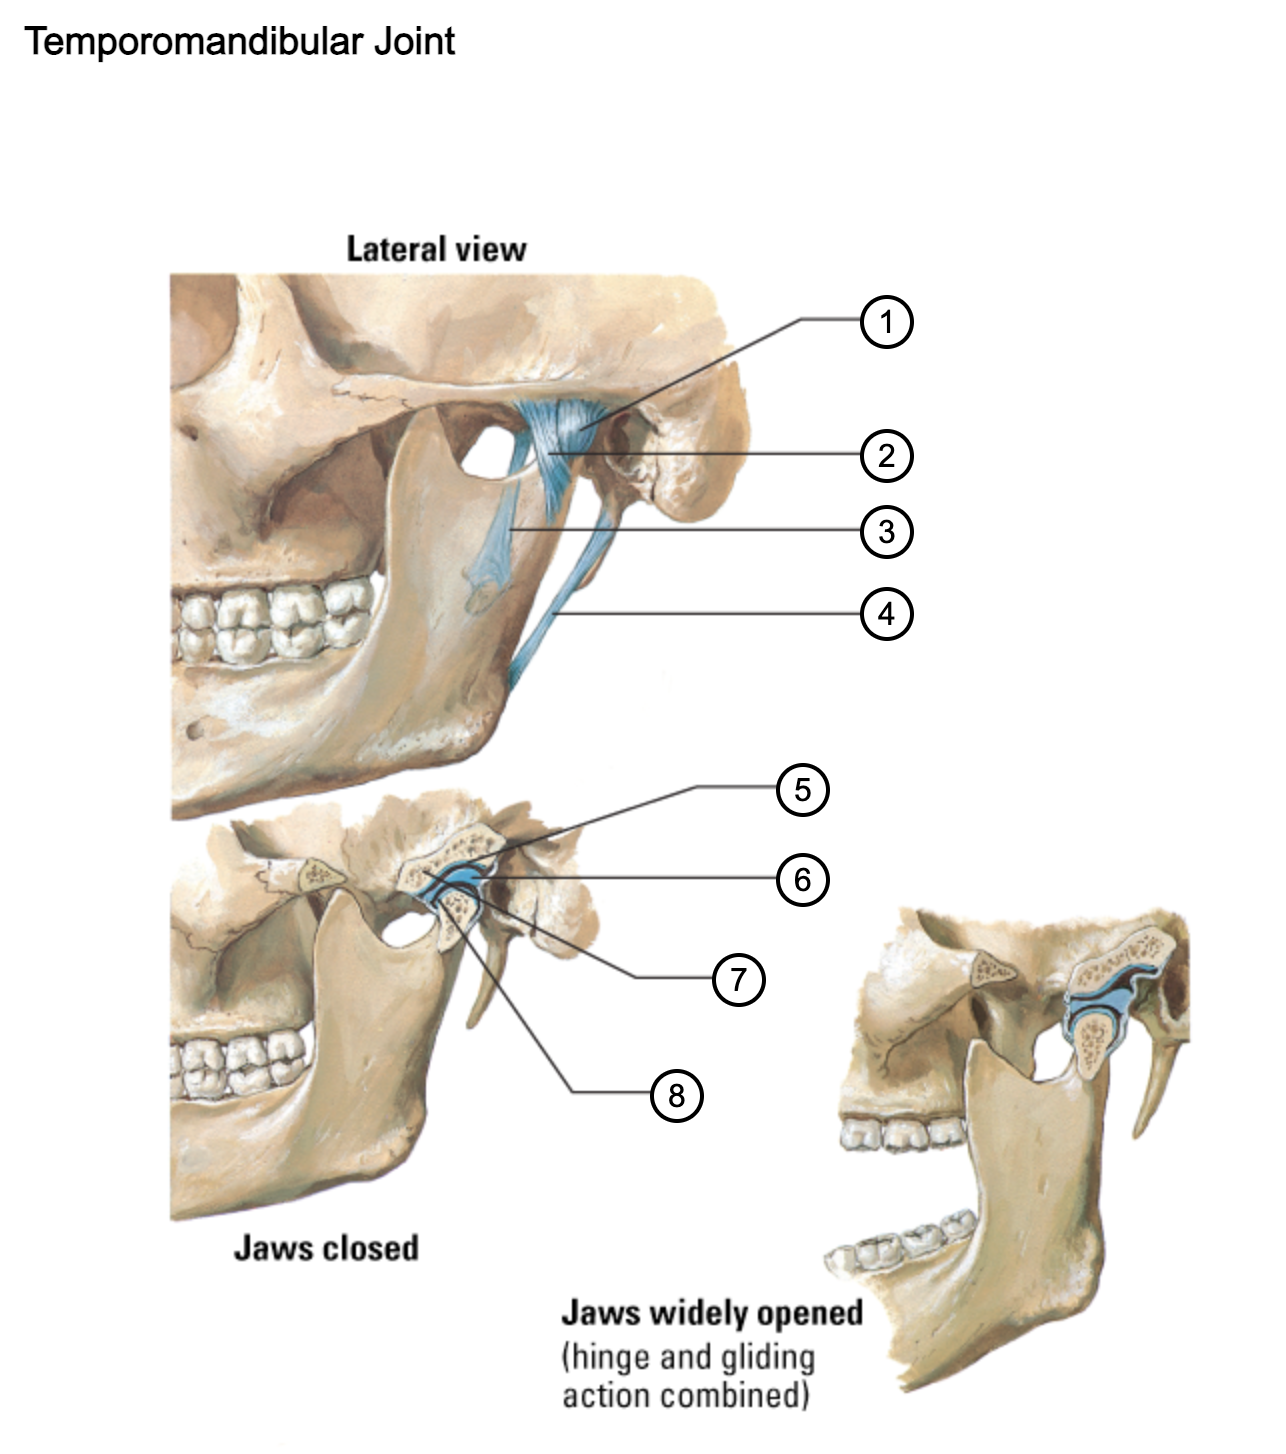

1

capsule of temporomandibular joint

2

lateral temporomandibular ligament

3

sphenomandibular ligament

4

stylomandibular ligament

5

mandibular fossa

6

articular disc

7

articular tubercle

8

capsule of temporomandibular joint